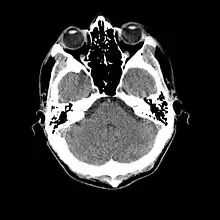

- Cranial computed tomography (CT, invented 1972) proved to be an excellent tool for diagnosing cerebral neoplasms in children, including those found in tuberous sclerosis.[46]